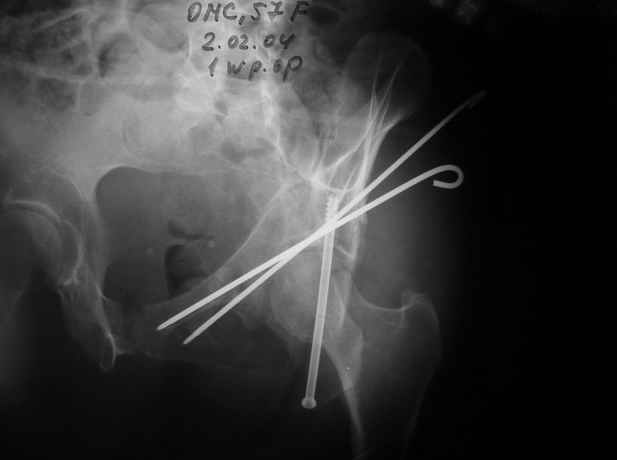

Уважаемые коллеги,Мужчина 36 лет от роду попал в ДТП 24.08.04 Рентгенограммы в приложении.

Диагноз- перелом с вовлечением таза, разрыв правого сакро-илиак сочленения vertical shear injury, перелом крыла подвздошной кости?, перелом ацетабулум Т type или Both column?, перелом шейки бедра, перелом проксимального отдела бедра.

перелом крыла правой подвздошной кости, перелом обеих колонн вертлужной впадины, двусторонний перелом лонных костей (С2.2) повреждение передних связок правого крестцово-подвздошного сочленения,

ипсилатеральный перелом шейки и диафиза бедра.